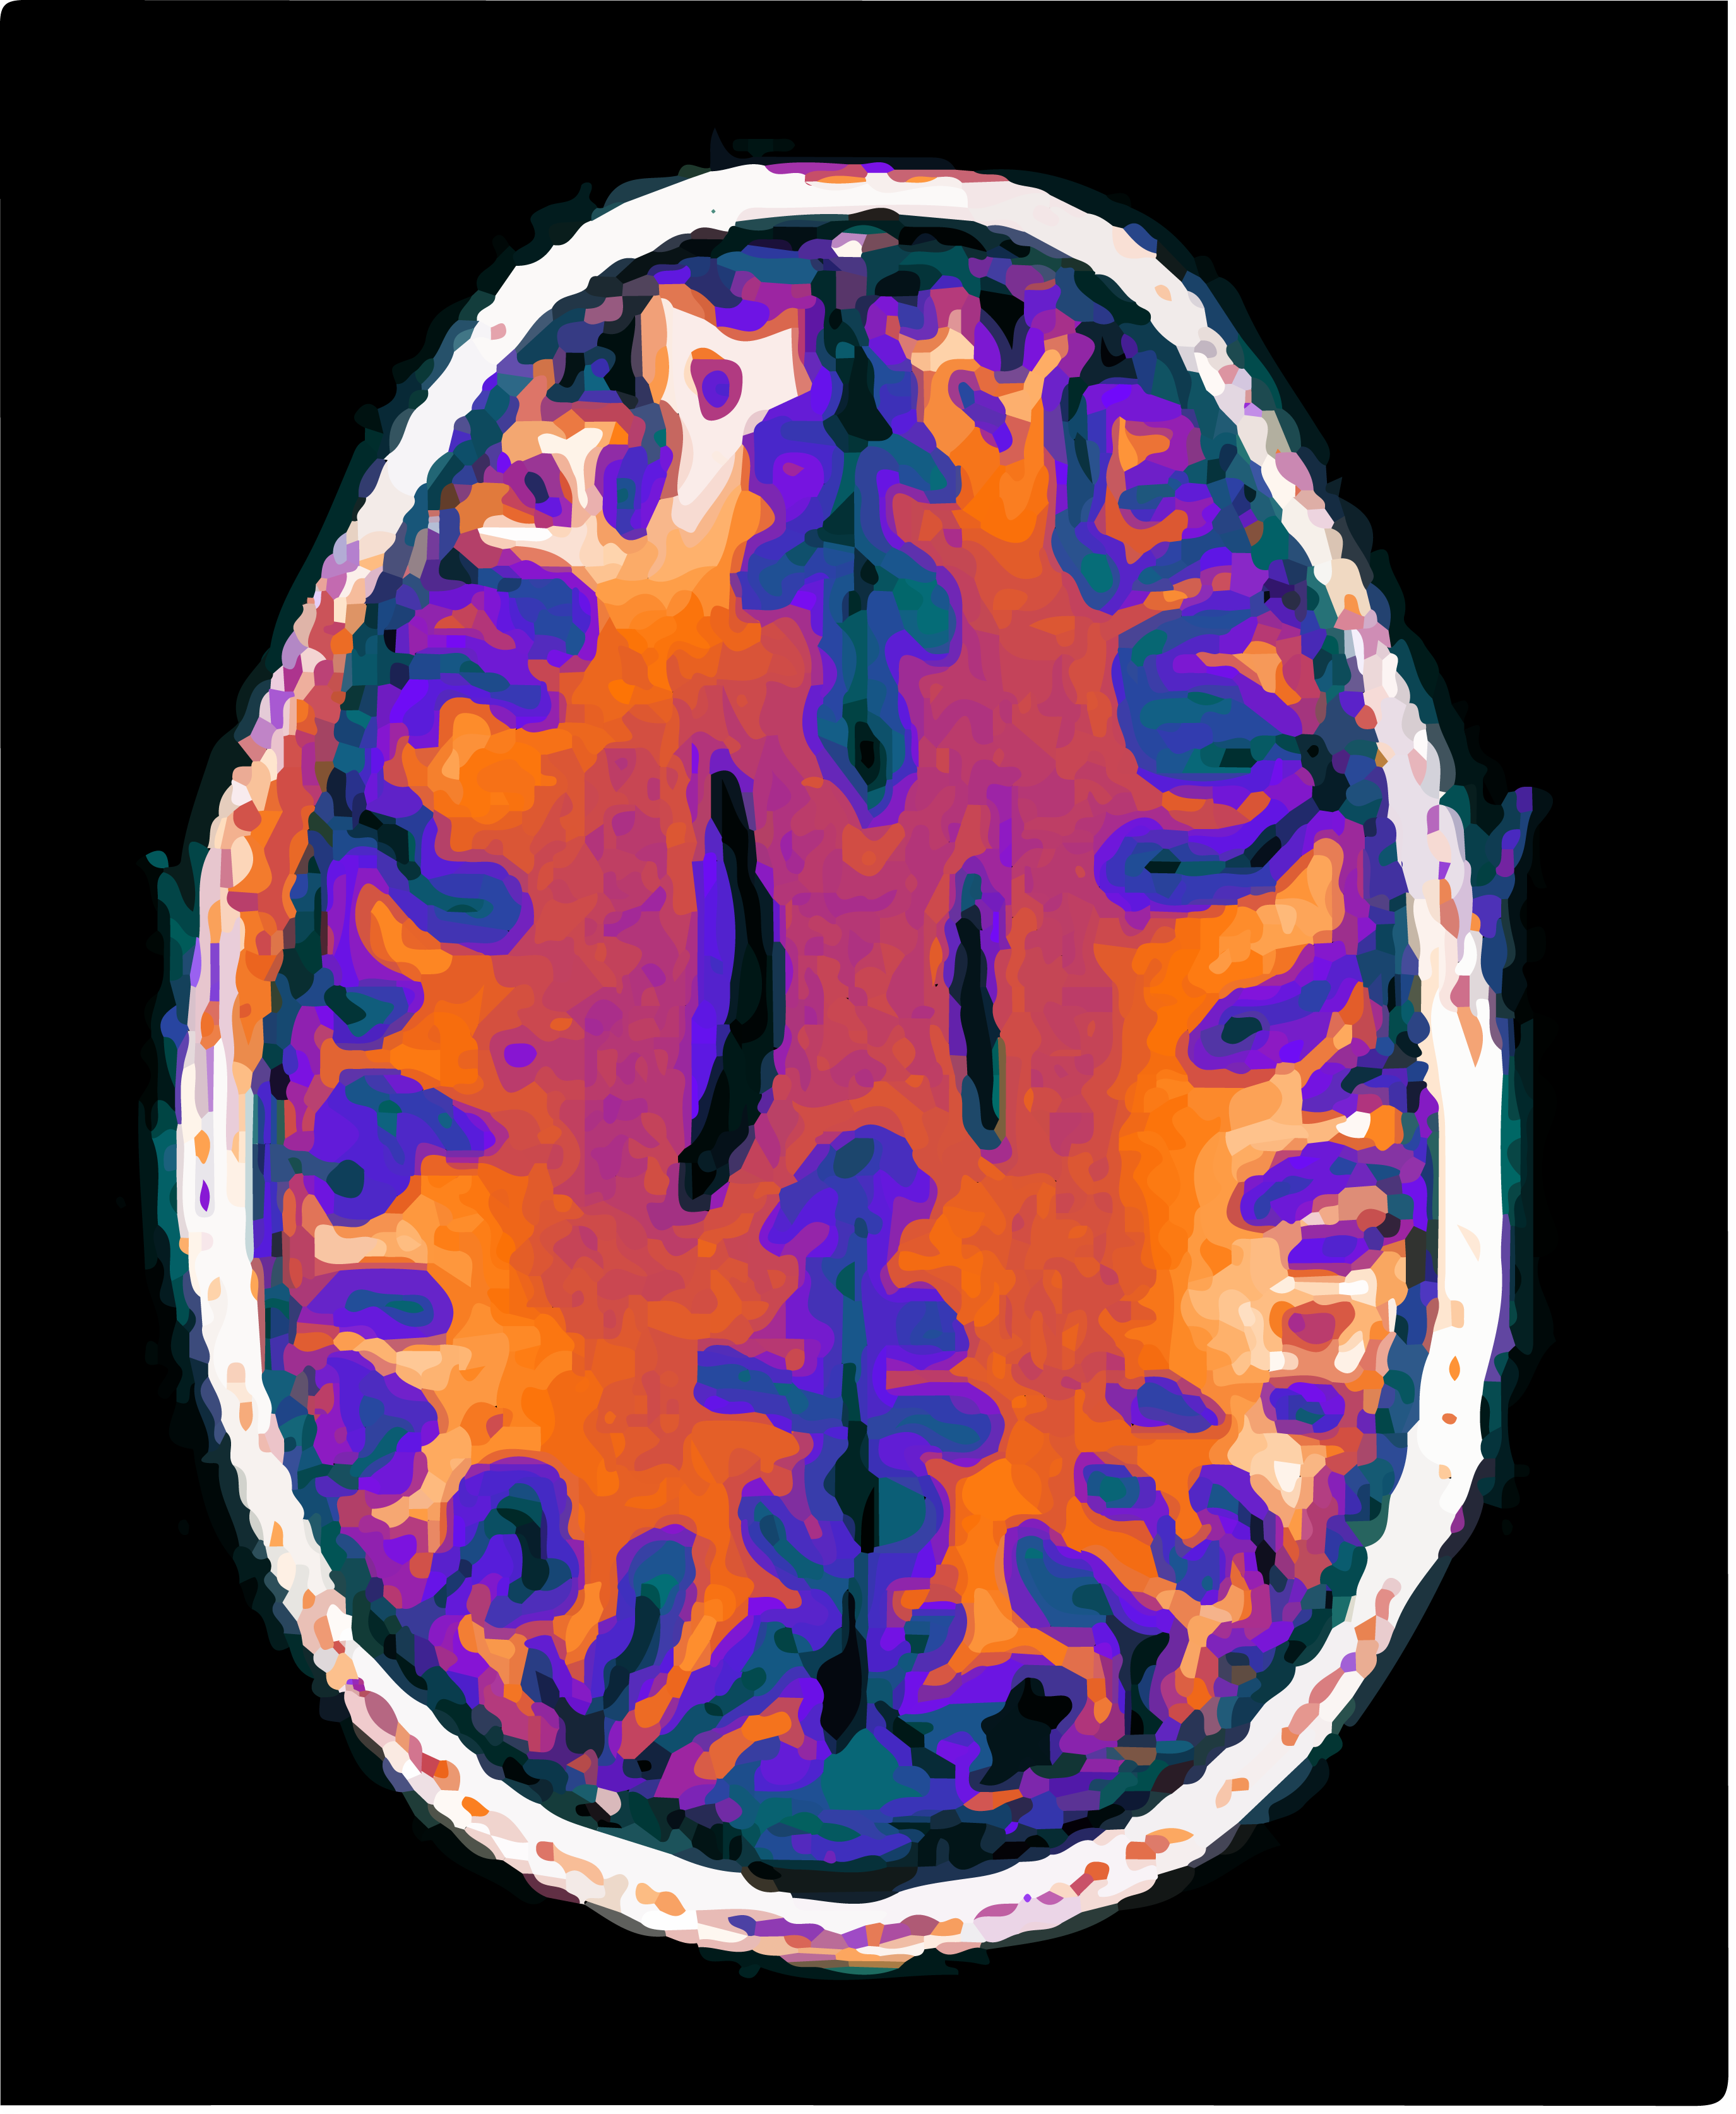

014: Brain Scans

Some visuals from a neuroscience study.

My friend sent in some images of his brain.

These are from a neuroscience research study.

They are T1-weighted structural images of his head 😳.

Beautiful and bizarre.

This was for academic research only (he's fine).